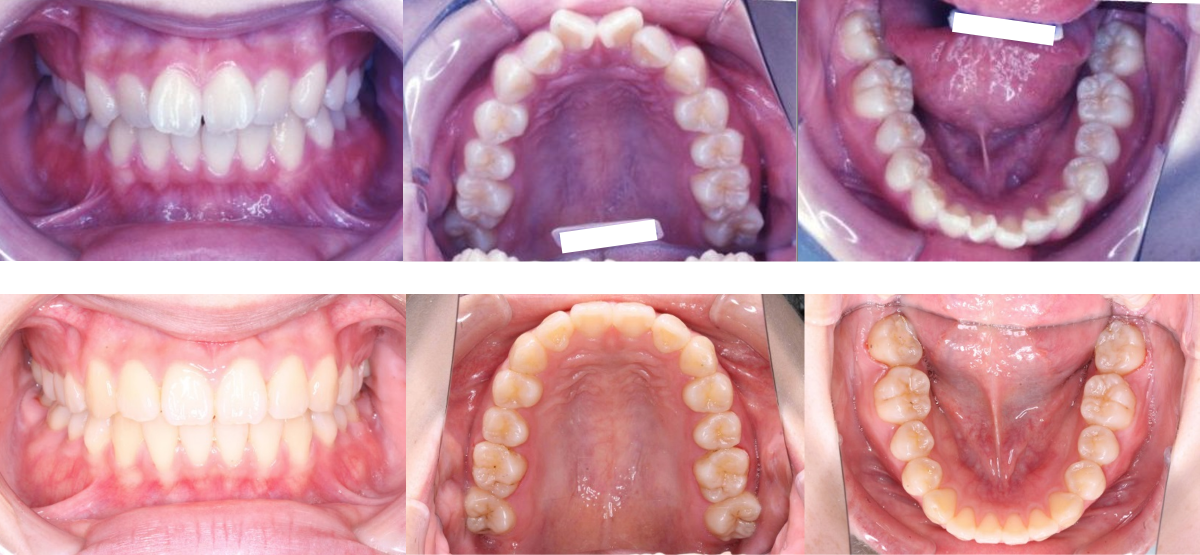

③叢生(でこぼこ)の矯正治療例(20代女性・治療期間1年6か月)

| 年齢・性別 | 20代女性 |

| 治療期間 | 1年6か月 |

| 抜歯 | なし |

| 治療費 | 50万円(調整費、保定費まで含む総額制) |

| 備考 | インビザライン |

| リスク・副作用 | 痛み・治療後の後戻り・歯根吸収・歯髄壊死・歯肉退縮 |